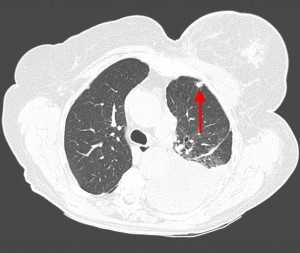

КТ ОГК. Множественные мягкотканные очаги в обоих легких у пациента с первичным раком предстательной железы

Вторичные узлы гематогенного характера чаще всего имеют ровные края, четкие контуры и однородную структуру. Возможны изменения структуры опухоли вследствие кровоизлияния в паренхиму, обызвествлений, некроза центральной части узла, а также рубцов. Края узла могут стать нечеткими, расплывчатыми, если опухоль провоцирует отек легочной паренхимы, либо «лучистыми», если имеет место опухолевый лимфангиит.

Слева - рак почки с метастазами в легкие, прогноз в данном случае неблагоприятный ввиду метастатического плеврита и дыхательной недостаточности. Определяются очаги с обеих сторон. Справа - мелко- и среднеочаговая диссеминация при раке печени.

Множественные гематогенные вторичные узлы при раке почки, компьютерная томография (КТ).